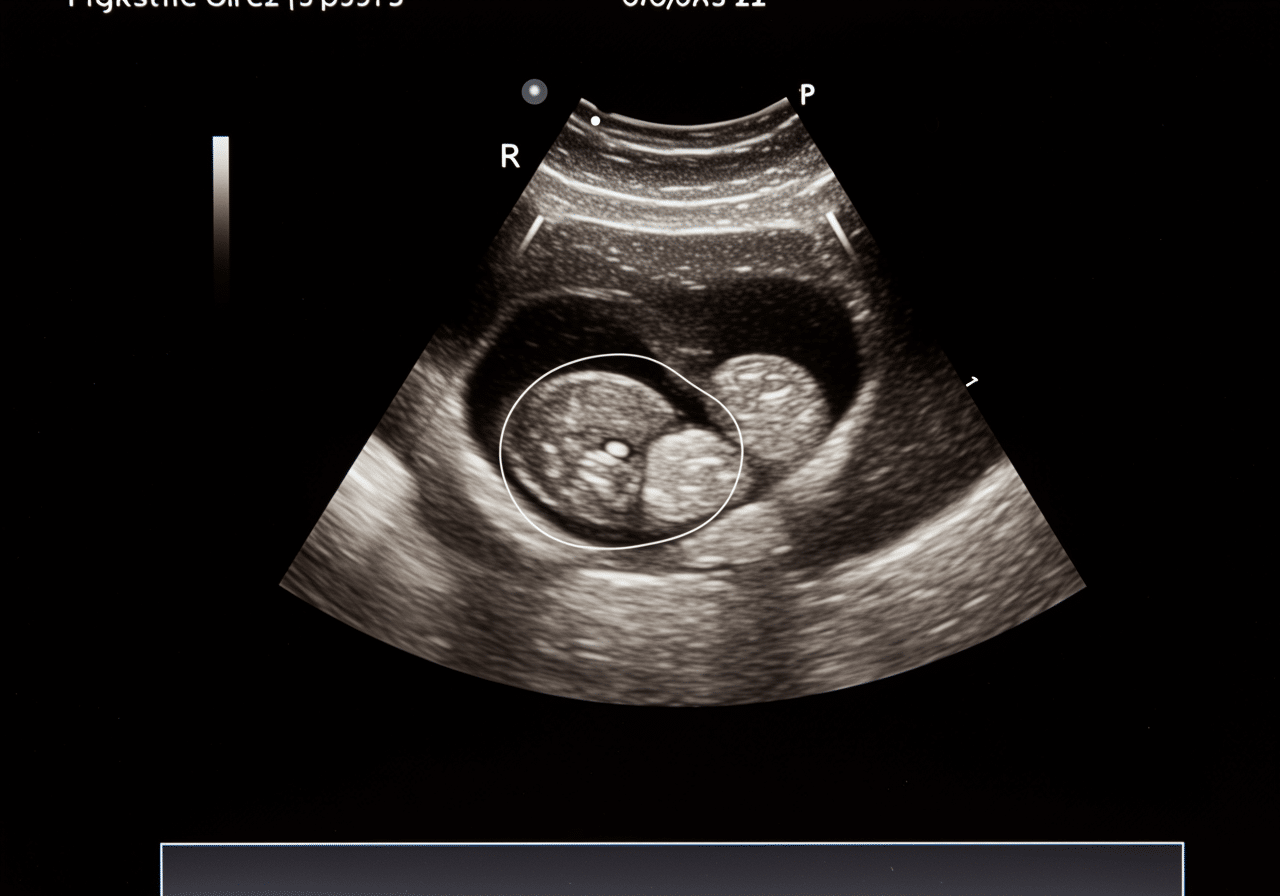

Emergency pelvic ultrasound room at Priority ER Odessa with advanced equipment

State-of-the-art pelvic ultrasound equipment available 24/7 at Priority ER for immediate gynecological evaluation